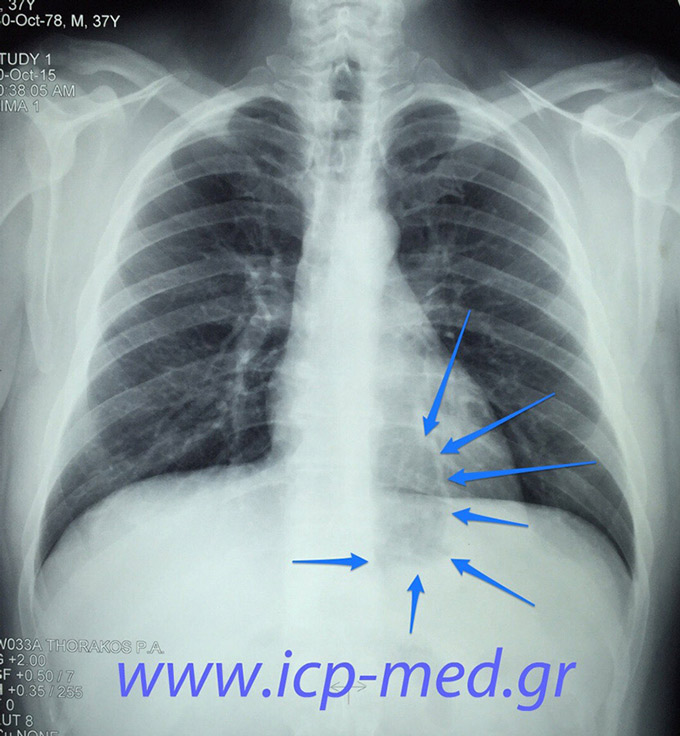

Sliding Hiatal Hernia

2. The same preop CXR. Arrows: intrathoracic part of stomach, missed earlier by many